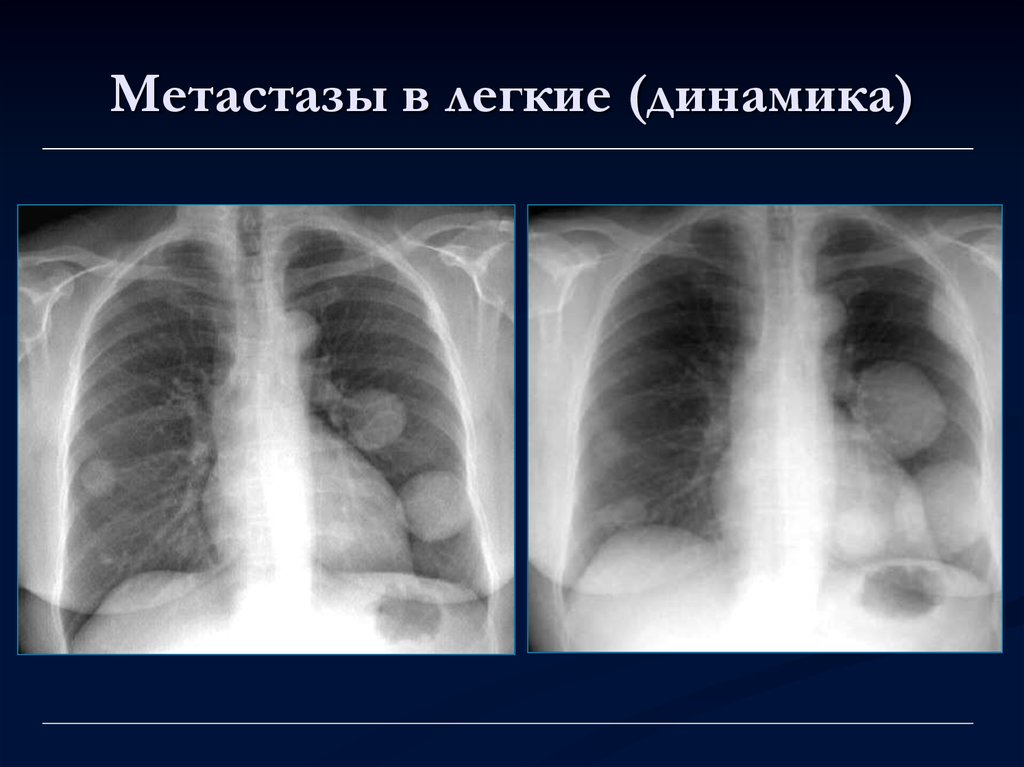

Рак Легких На Рентгене Ранняя Стадия Фото👉🏻👉🏻👉🏻 ВСЯ ИНФОРМАЦИЯ ДОСТУПНА ЗДЕСЬ, ЖМИТЕ 👈🏻👈🏻👈🏻Рак Легких На Рентгене Ранняя Стадия Фото